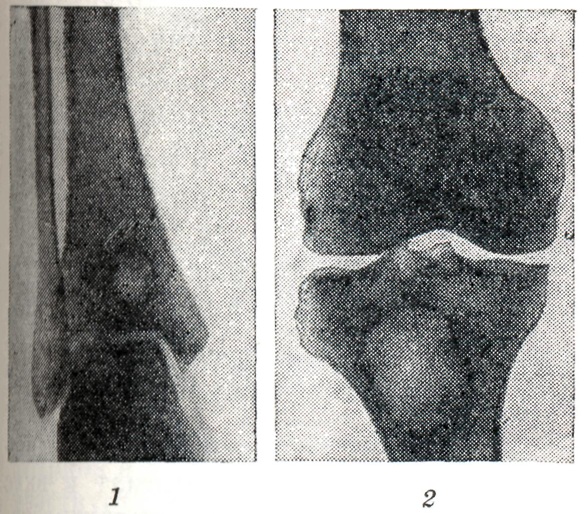

На рентгенограммах, Б. а. представляется в виде изолированной округлой или овальной полости в губчатом костном веществе метафиза или метаэпифиза (рис.,1 и 2) диаметром 2—3 см. Обычно расположен поверхностно под корковым слоем кости. Поражает чаще всего большеберцовую, реже бедренную и значительно реже плечевую, лучевую, локтевую и другие длинные трубчатые кости. Наибольший размер полости совпадает с длинником кости. В полости, как правило, не выявляется секвестров, внутренние контуры её ровные, вокруг неё вырисовывается узкая полоска склерозированного губчатого вещества, к-рая постепенно переходит в нормальную костную ткань.

При небольших размерах абсцесса периостальной реакции обычно не наблюдается. По мере увеличения полости и обострения воспалительного процесса развивается ограниченный оссифицирующий периостит. Вследствие этого возникает цилиндрическое или веретенообразное утолщение кости на уровне полости.